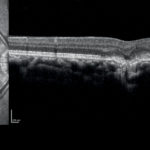

Neovascolarizzazioni coroideali nelle infiammazioni oculari